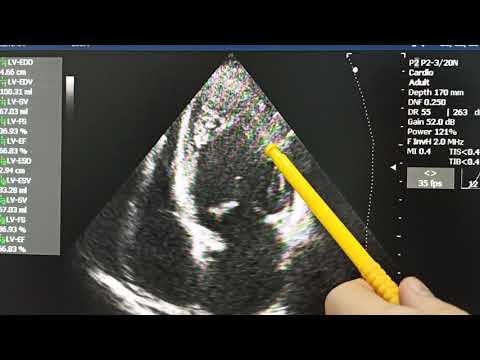

Фракция выброса левого желудочка по Тейхольцу, Симпсону и Думеснилу доплеровский метод

ЭхоКГ FOCUS